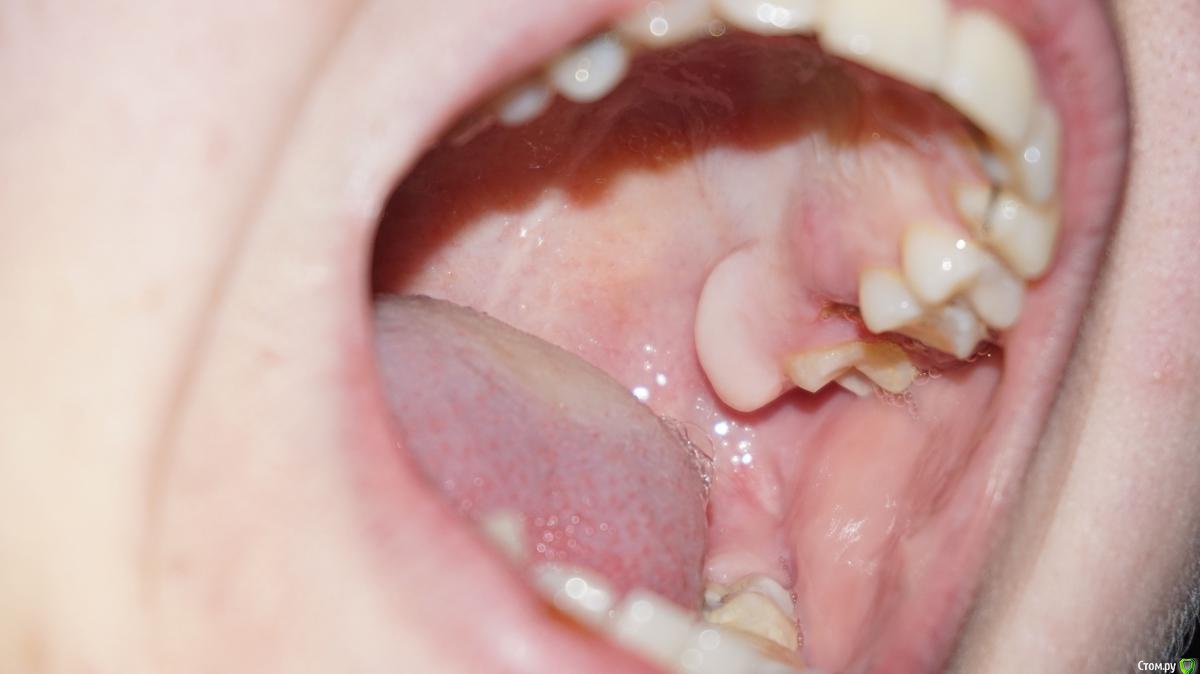

Здравствуйте, помогите, пожалуйста, с консультацией.(фото ниже) Два дня назад произошло небольшое воспаление десны на верхней челюсти.Боли нет, только при расшатывании кусочка зуба, есть припухлость, еще беспокоит увеличение кости.Не дай Бог, зуб мудрости, очень боюсь этой операции.